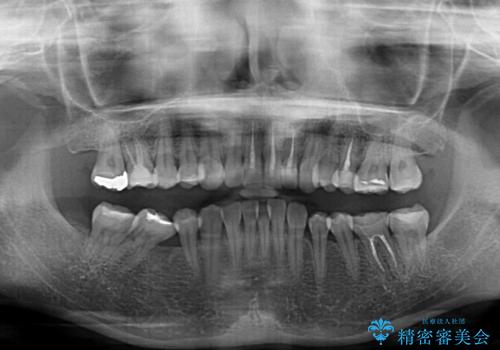

- 全体的なデコボコと、奥歯の欠損を放置した結果倒れ込んだ奥歯などを気にして来院された患者様です。

ワイヤー矯正の方が理想的な仕上がりとできる状態でしたが、上顎前歯にクラウンが装着されているため、インビザラインにて矯正治療を行うこととしました。

インビザラインのみで対応できないときにはワイヤー矯正を併用することとし、矯正治療後にはオールセラミッククラウンによる補綴治療を行うこととしました。